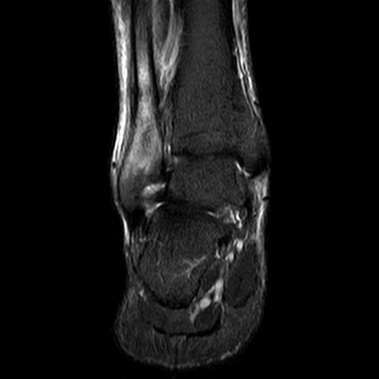

This decision was based on evidence suggesting that teriparatide can accelerate fracture healing by stimulating osteoblast activity and enhancing bone remodeling. Over the course of the treatment, the patient continued her nutritional monitoring, ensuring adequate intake of calcium and vitamin D to support bone health. After four months of teriparatide treatment, follow-up imaging showed complete consolidation of the fracture.

The patient reported significant pain reduction and was able to gradually return to her running routine under the guidance of her healthcare team. Physical therapy was also incorporated to strengthen the surrounding muscles and prevent future injuries. Throughout the treatment, the patient's progress was closely monitored, and she experienced no adverse effects from the teriparatide therapy.

Her recovery was marked by a steady improvement in pain levels and functional outcomes, allowing her to resume her athletic activities with confidence. (Figure 1,2)

Figure 2 MRI of Consolidated Fibula Fracture: This case discusses a stress fracture of the fibula, which typically shows radiological changes late, often not visible before four weeks. The MRI shows marked edema in the distal aspect of the fibula, consistent with a stress fracture healing process.